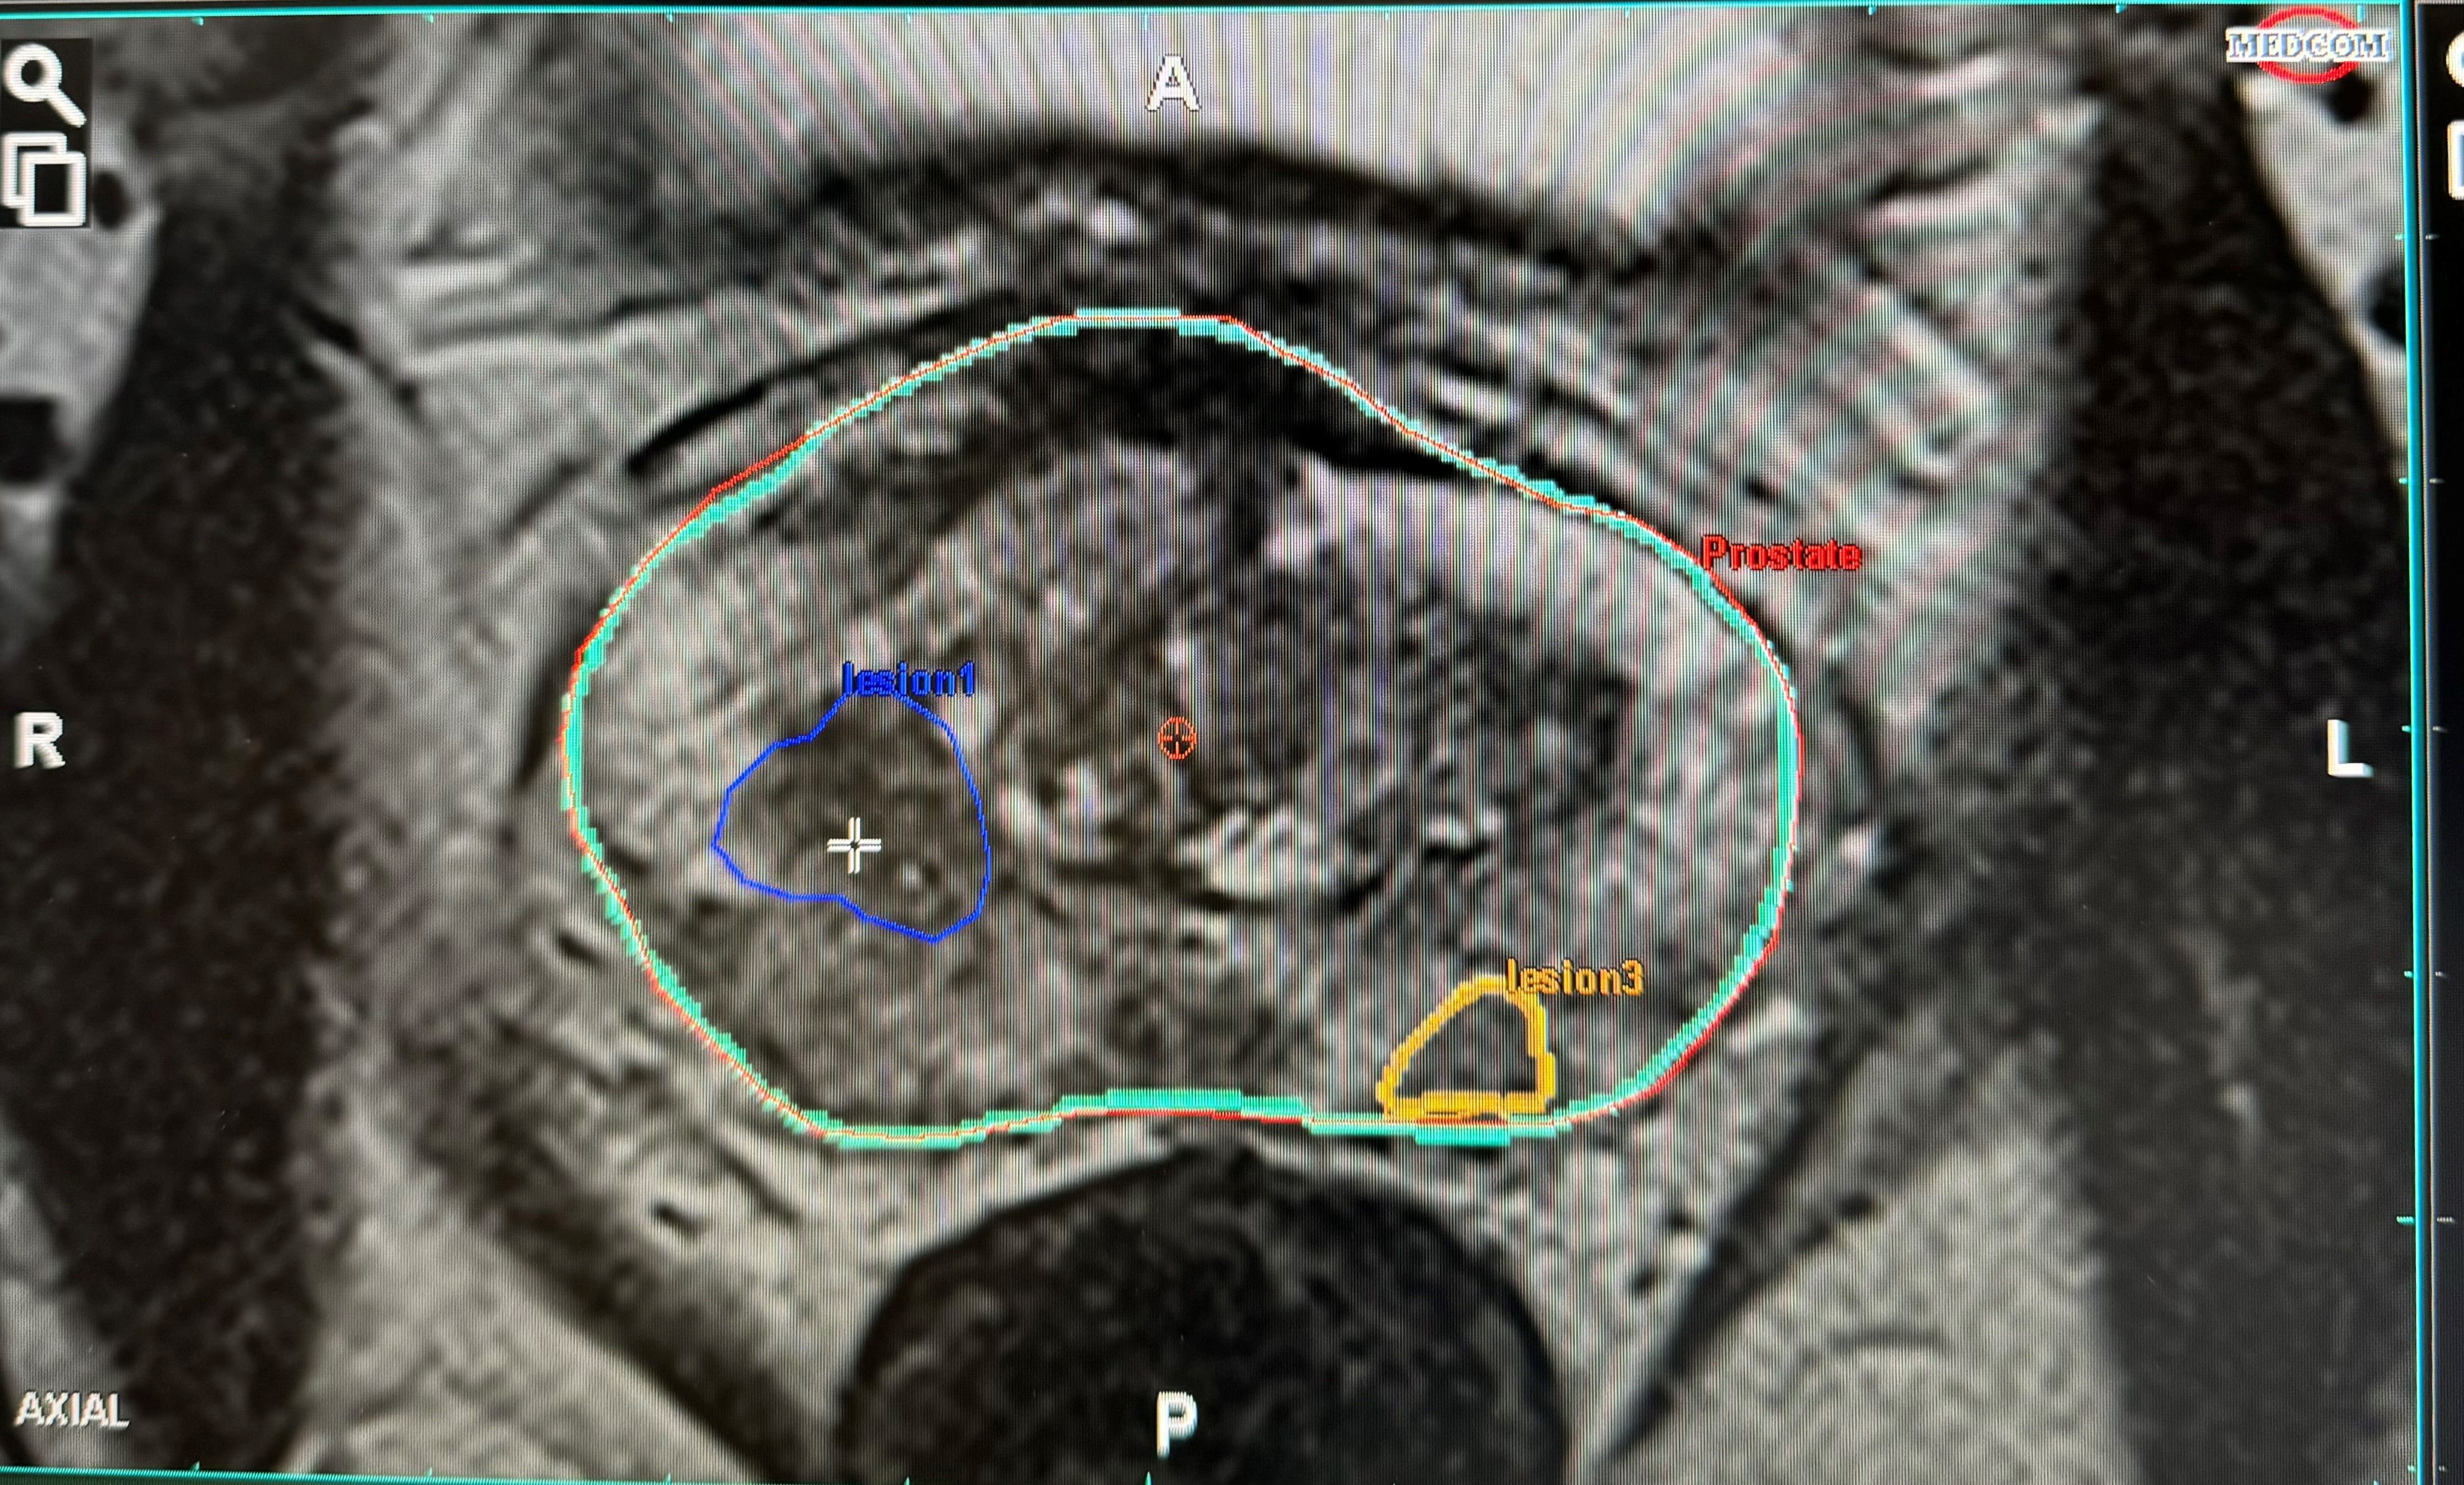

Nach der Anfertigung Ihres mpMRTs der Prostata lesen wir die gewonnenen Bilder in eine KI-gesteuerte Planungssoftware ein. Hierbei fokussieren wir uns auf die korrekte Kontur Ihrer Prostata, Ihrer Harnröhre und dem Areal, welches von Ihrem Radiologen, als auch von künstlicher Intelligenz als auffällig beschrieben wurde. Diese angefertigte Kontur wird dann in das Ultraschallgerät vor Ihrer Biopsie übertragen. Mit Hilfe dieser Konturen sind wir in der Lage, auch kleinste auffällige Areale gezielt zu biopsieren.

Auf Grundlage dieser Bildgebung können wir eine gezielte Gewebentnahme (Biopsie) durchführen. Dies geschieht mittels einer moderner, computergestützter Bildfusion – hierbei werden die mpMRT Bilder und Ultraschallbilder, welche wir für die Biopsie erzeugen, übereinander gelegt (Fusion). Die Biopsienadel kann somit bei der Gewebeentnahme genau auf den Tumor ausgerichtet werden und so die Treffsicherheit um ein vielfaches maximieren.